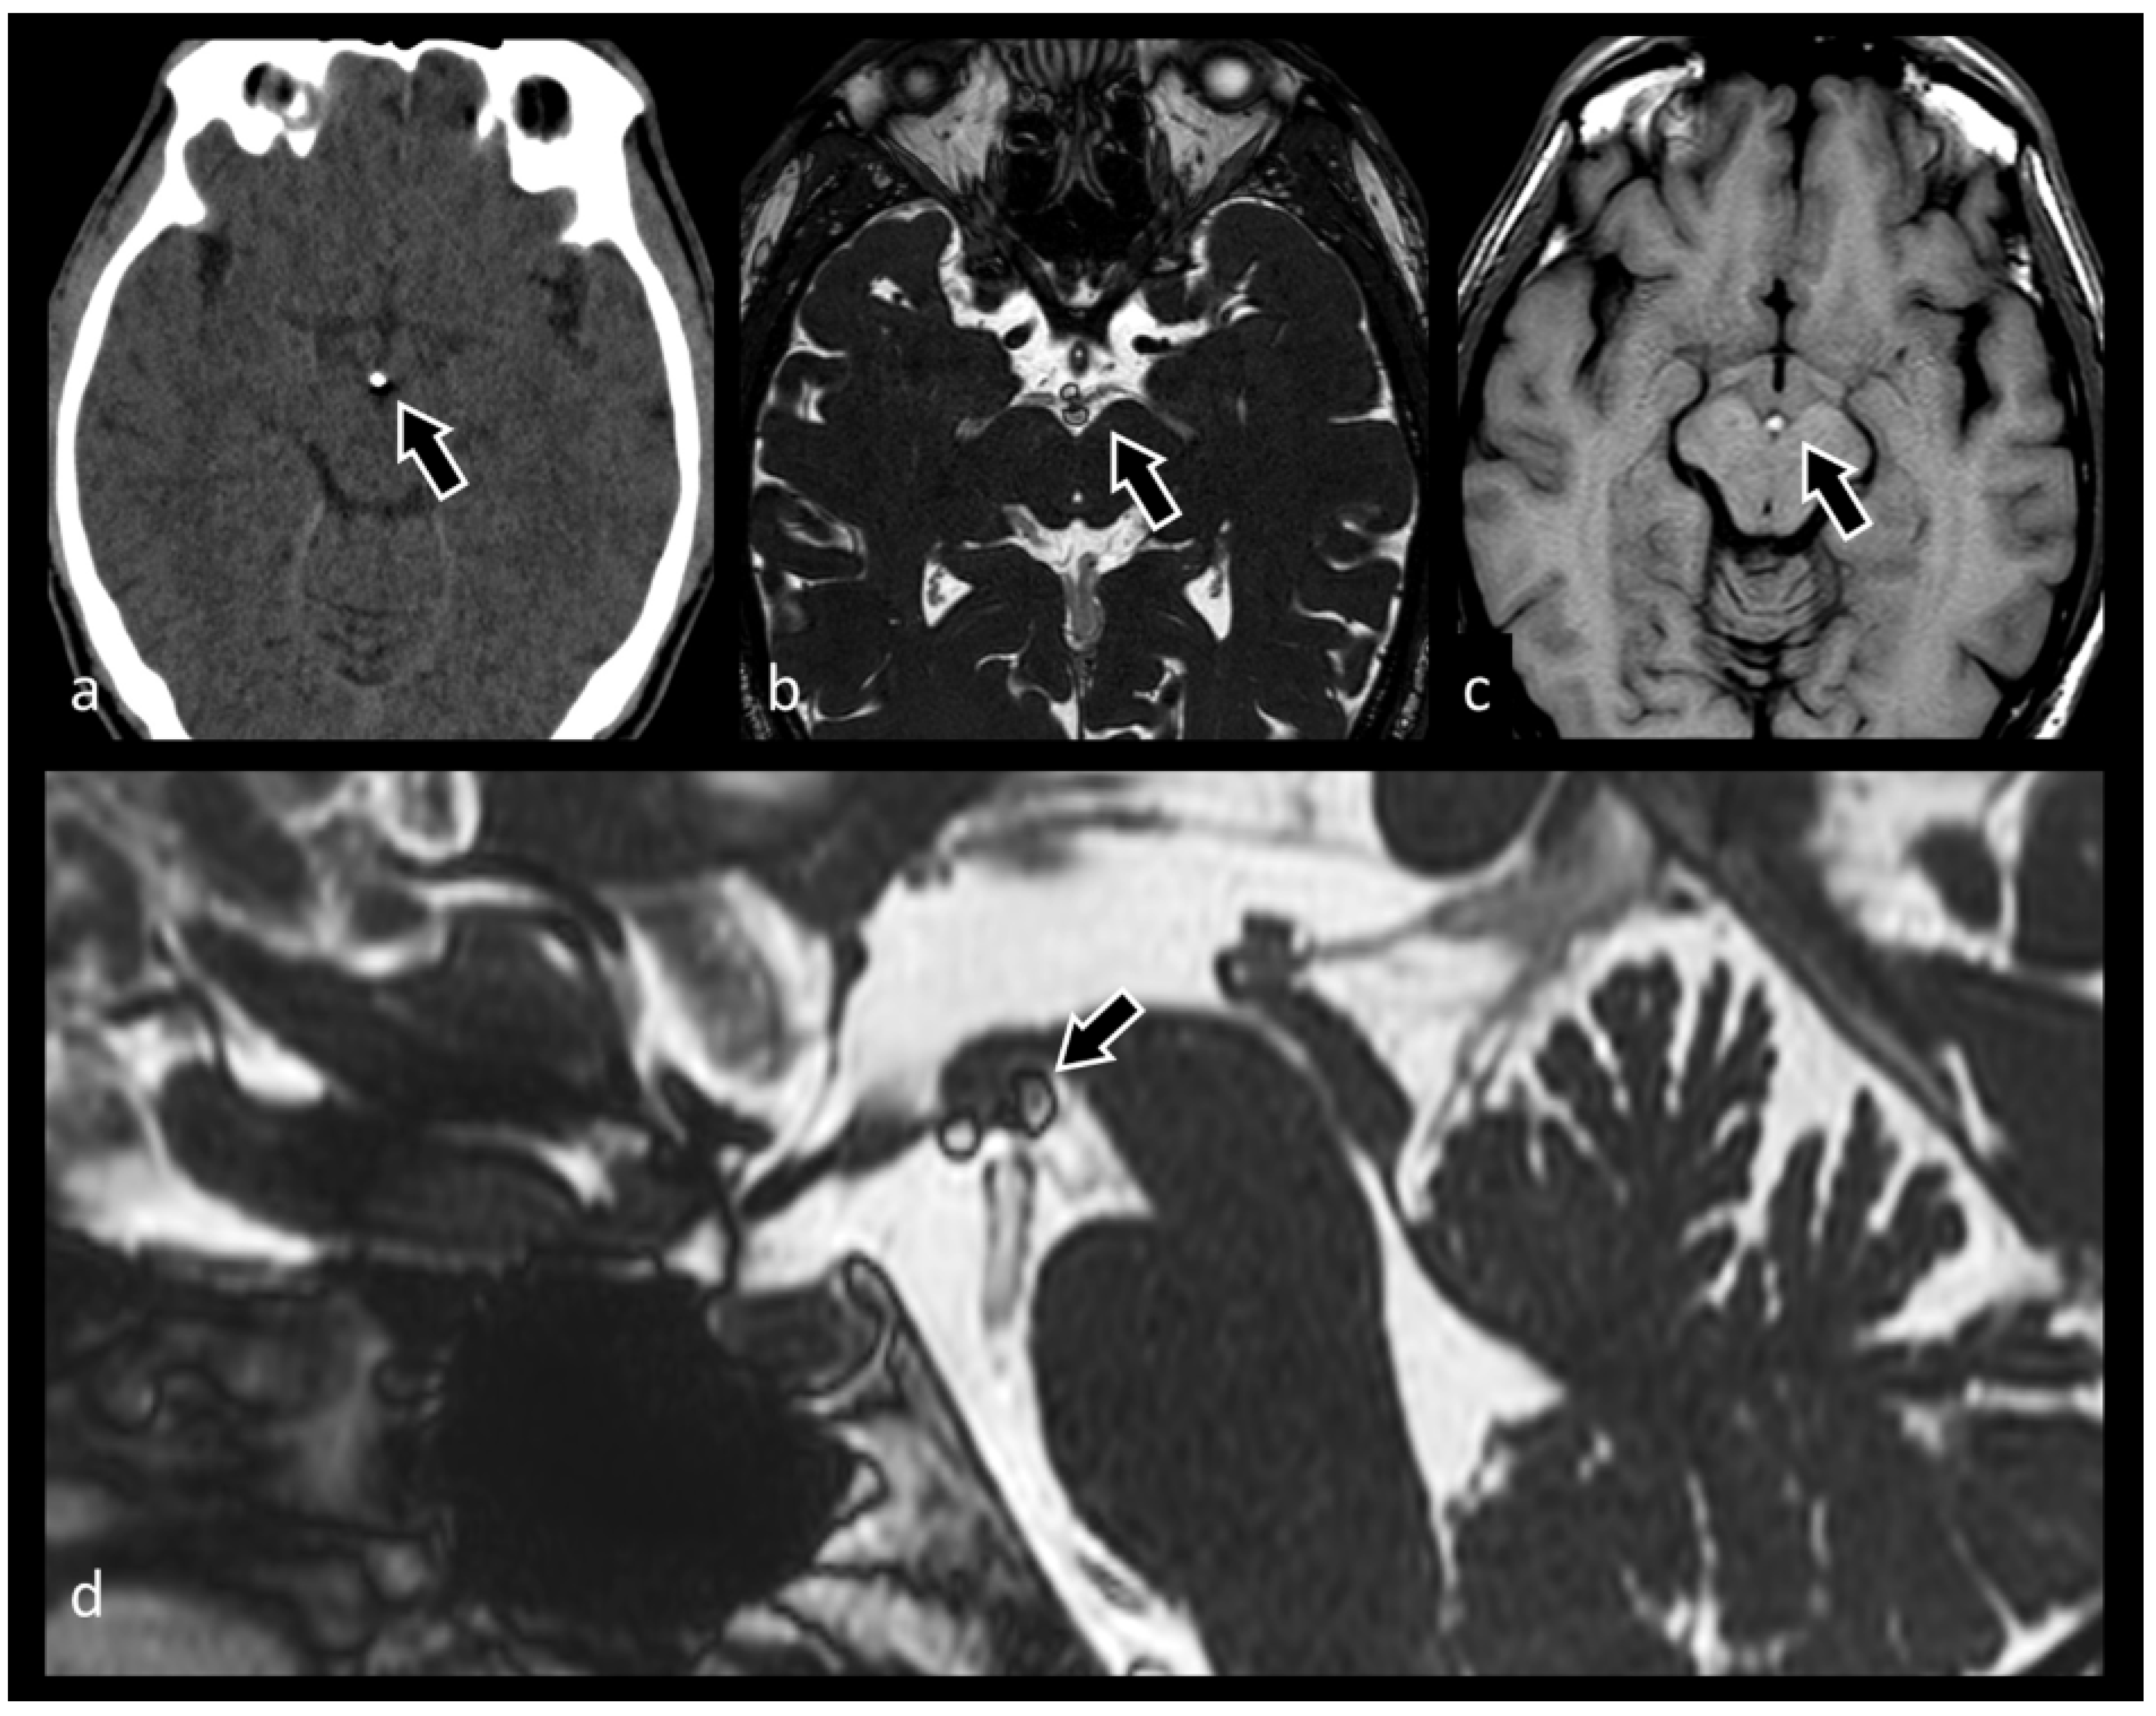

3.6. Neurocysticercosis

3.7. Evaluation of Brain Tumors